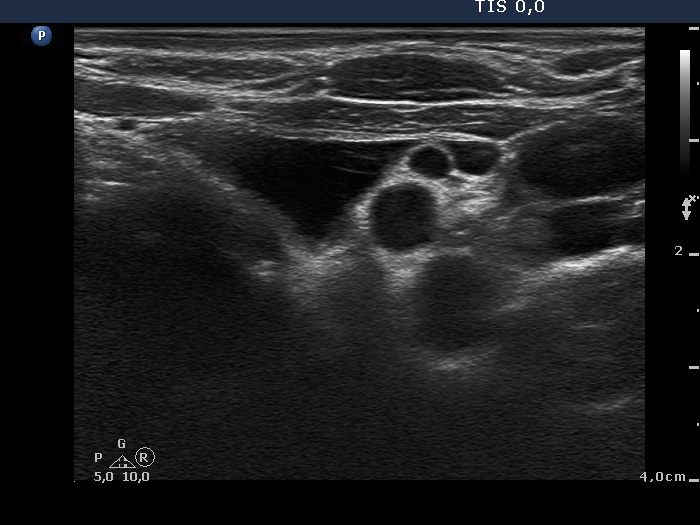

Ultrasonography. The thyroid was echonormal and contained a minimally hypoechogenic nodule in the ventral part of the right lobe. There was a cystic lesion under the lower pole of the left lobe.

Cytology of the thyroid lesion resulted in benign colloid goiter. 16 mL watery fluid was aspirated from the mass under the thyroid. Wash-out parathormone level of the cystic fluid was 917 pg/mL, while serum parathormone was 24.3 pg/mL (normal value: 15-65).